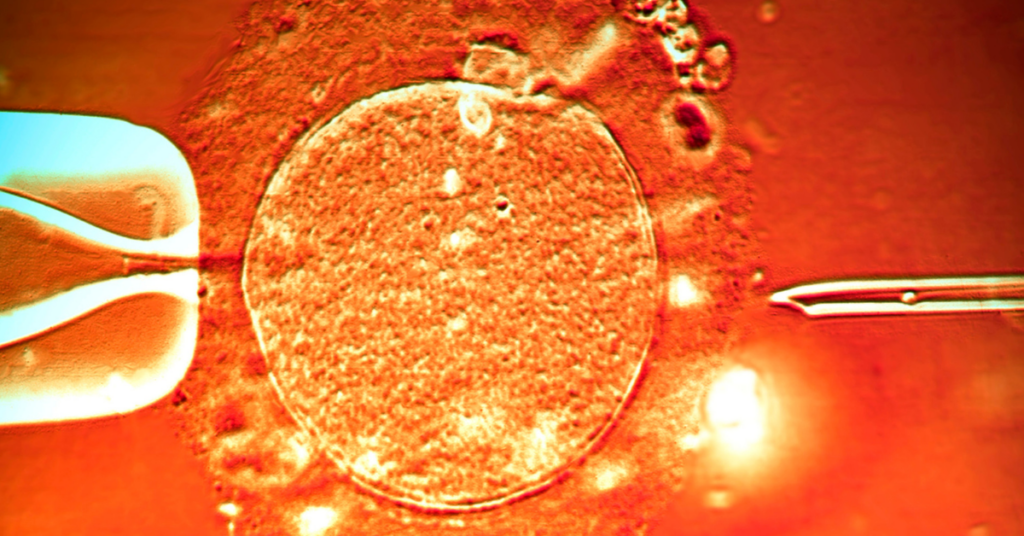

Dojenje je najprirodniji dar i najzdraviji način ishrane novorođenčeta, znajući to trudnice se za njega pripremaju još pre porođaja. Ipak, kada dođe vreme prakse, kada se beba nađe u naručju praktična podrška je ključna za njegovo uspostavljanje. Ipak, kako uspostaviti dojenje kada vas laktacijska sestra rasplače, bebu na podoj donesu nahranjenu ili u toku boravka u porodilištu konstantno dobijate kontradiktorne savete, a sve su to doživljavale upravo Bebac mame tokom boravka u porodilištu.

Kažu da dojenje i majčino mleko unapređuju zdravlje majke, deteta, i zdravlje tokom čitavog života. Od naše podrške zdravstvenih radnika i društva zavisi da li će majke doživeti dojenje kao prijatno i korisno iskustvo, ili suprotno tome kao dužnost tj. obavezu ili normu koju moraju da se ispune. Učinimo da se nijedna majka ne oseća neuspeh i postiđenosti tokom uspostavljanja dojenja – krenimo od edukacije i empatije i sve ostalo će biti lakše.